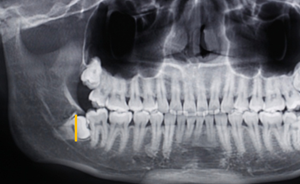

第二:充分暴露牙體組織后,沿47牙長(zhǎng)軸方向?qū)?8進(jìn)行分冠,分冠線如下:

第三:分冠后近中牙體組織若無法順利脫位,可進(jìn)一步將近中牙冠分為頰舌兩部分,依次脫位。